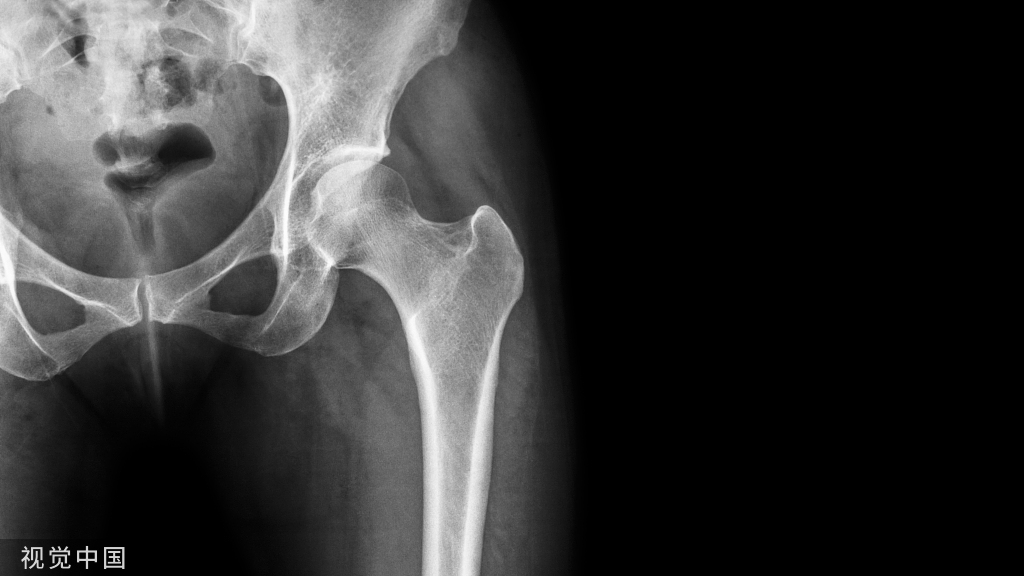

近年来,糖尿病的骨折风险越来越受到重视,糖尿病患者严重骨折与全因死亡率有关。T1DM和T2DM发生脆性骨折的风险都会增加,《糖尿病患者骨折风险管理中国专家共识》[1]指出虽然双能X线骨密度仪测得的骨密度能够在一定程度上反映非糖尿病患者的骨折风险,但却会严重低估了糖尿病患者的骨折风险。因糖尿病患者可以在相对于非糖尿病患者较高的骨密度下发生骨折,而且各种降糖治疗也可能对骨代谢产生影响,如何通过生化标记物早期判断糖尿病患者的骨折风险,并由此采取有效措施遏制糖尿病骨折的发生发展显得尤为重要。

关于T1DM和T2DMO之间的差异,更具体地说是关于两种疾病在代谢紊乱中骨脆性的病理生理学,已经有大量的研究进行证实:T1DM是一种以T细胞介导的β细胞破坏为特征的自身免疫性疾病。由于T1DM的发病通常发生在儿童期和青春期,骨量的累积受到影响,导致炎症、胰岛素缺乏和胰岛素样生长因子-1(IGF-1)水平降低,引起骨量和骨矿化程度降低。在T2DM的早期虽与T1DM相比骨损害表现不太明显,但随着病程的进展,血糖控制越来越差,糖尿病骨折的风险也显著增加。与T1DM和T2DM的慢性高血糖相关的一个共同因素是骨组织材料特性的改变,这与临床中常见的绝经后骨质疏松引发的骨折类型有较大的差异。